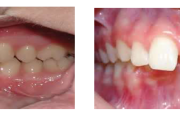

Puudub ülemine tsentraalne intsisiiv, kuid külgmised lõikehambad on juba lõikunud.

Turritavad ülemised lõikehambad.

Puudub ülemine tsentraalne intsisiiv